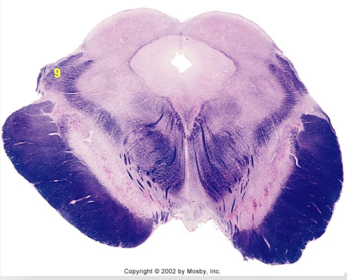

| Nucleus gracilis | |

| Accessory nucleus | |

| Medial longitudinal faciculus | |

| Pyramidal decussation | |

| Medullary pyramids | |

| Anterior spinocerebellar tract | |

| ALS | |

| Posterior spinocerebellar tract | |

| Spinal tract of V | |

| Spinal nucleus of V | |

| Nucleus cuneatus | |

| Fasciculus cuneatus | |

| Fasciculus gracilis | |

| Central canal | |